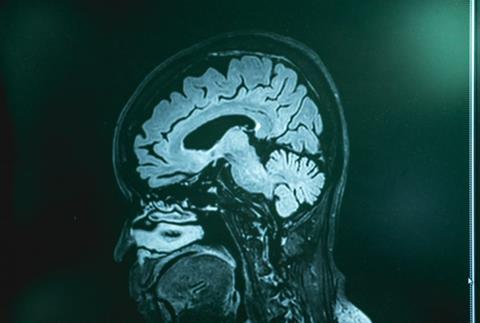

In ALS, neurons in the motor cortex and spinal cord degenerate, resulting in paralysis. In FTD, neurons located in the parts of the brain involved in cognition, language and personality are affected. Although the abnormal accumulation of the TDP-43 protein in neurons in the central nervous system (CNS) is a common factor in most of ALS patients, and in around half of FTD patients, the underlying cellular mechanisms driving neurodegeneration remain largely unknown.